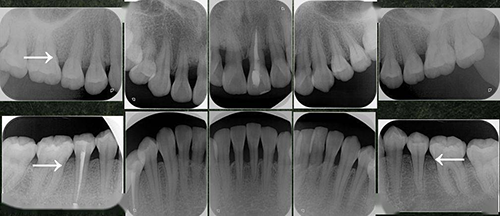

4.好发牙位:局限型侵袭性牙周炎的特征是“局限于第一恒磨牙或切牙的邻面有附着丧失,至少波及两个恒牙,其中一个为第一磨牙。其他患牙不超过两个”。广泛型的特征为“广泛的邻面附着丧失,侵犯第一磨牙和切牙以外的牙数在三颗以上”,也就是说,侵犯全口大多数牙。